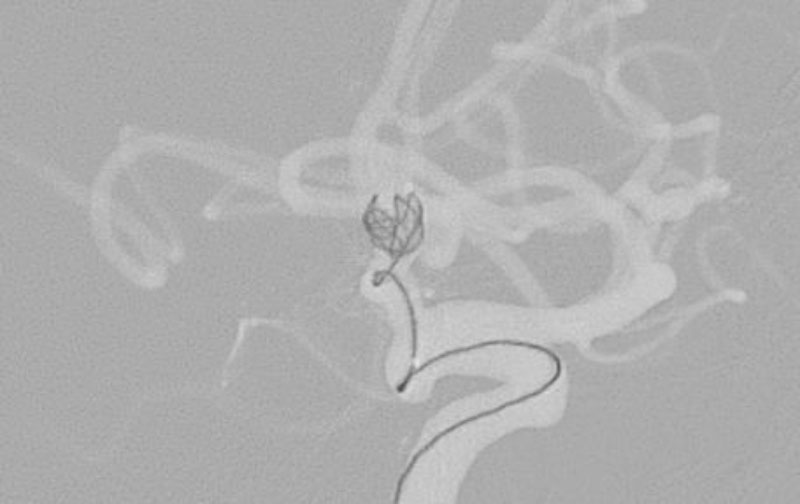

No.1596 手術中

くも膜下出血

左中大脳動脈瘤破裂

40代